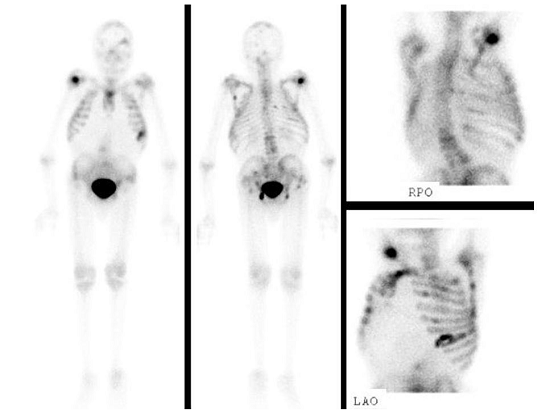

Laboratory studies were within normal limits except for anemia with hemoglobin of 8.5 gm/dL (normal range [NR]; 13.5 to 18.0 gm/dL) and leukopenia with a white blood cell count of 1700/mm3 [NR]; 4000-11000/mm3). Imaging studies revealed cardiomegaly, multifocal osseous metastatic disease (Figure 2), degenerative disc disease resulting in varying degrees of central canal and foraminal stenosis, wedge deformities of C2 and C4 without evidence of displaced fracture, chronic osseous changes of upper lumbar spine with significant vertebral body compression, bilateral hip disarticulations and small liver metastases.